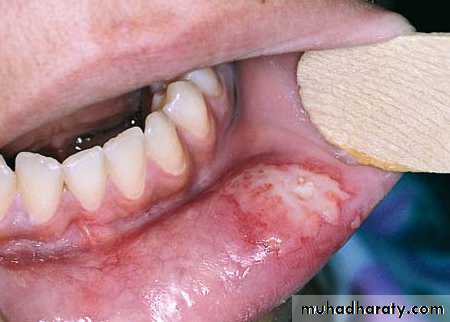

15- Damage to gums, lips, inferior alveolar nerve, lingual nerve ,tongue and floor of the mouth..Damage to the gum can be avoided by careful selection of the forceps and good gum separation before tooth extraction.

The lip may be injured or crushed by the forceps , or it may be burned if instrument not allowed to cool before use after being sterilized.